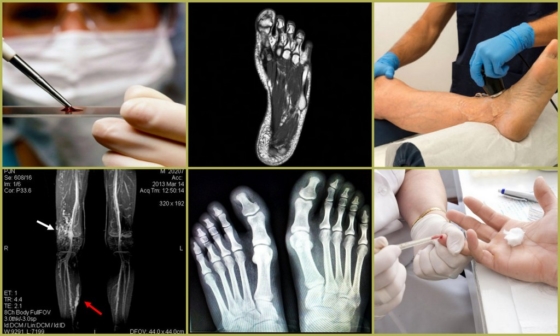

Для подтверждения диагноза показаны следующие методы:

- Рентген и КТ (компьютерная томография) ног – помогают выявить признаки поражения костей и суставов. Исследование можно дополнить введением контрастного вещества, которое покажет состояние сосудов;

- УЗИ (ультразвуковое исследование) и МРТ (магнитно-резонансная томография) – для обследования мягких тканей;

- Анализы крови – покажут анемию и другие дефицитные состояния, наличие воспаления.

Грамотная диагностика – первый шаг к тому, чтобы избавиться от судороги в пальцах ног. После её проведения доктор назначит необходимое лечение.